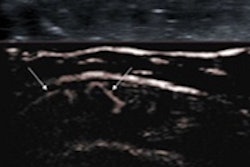

Side-by-side fusion imaging of real-time high-frequency ultrasound and MR images show the pediatric spine in a neonate with meningitis. Image courtesy of GE Healthcare.Concerned that ordering musculoskeletal ultrasonography is often based on the experience of a referring physician or sonographer, the European Society of Musculoskeletal Radiology (ESSR) selected a panel of experts from Austria, Belgium, Denmark, France, Italy, the Netherlands, and the U.K. in 2008 to work on the guidelines. Recommendations were based on the clinical condition, its level of evidence, the strength of the recommendations, and the percentage of agreement. Each clinical indication was then given an appropriateness grade, from zero (ultrasound not indicated) to three (ultrasound = first exam choice).